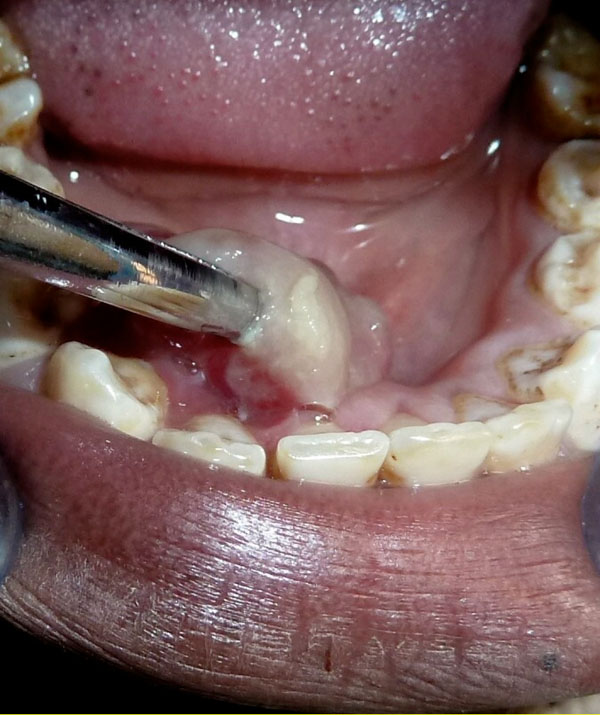

Clinical intraoral image of the exophytic lesion in relation to lingual area.

Clinical intraoral image. The lesion was pedunculated involving the lingual mucogingival line and inserted on the keratinized mucosa.

An exophytic kidney-shaped lesion with a lobular contour and a glossy gray to reddish-purple surface measuring 25 to 30 mm in diameter was located in the anterior lingual right jaw, inserted through a pedunculated base on the keratinized mucosa also involving the mucogingival line (Fig. 2). The mass was painless on palpation with a smooth compressible surface but with certain firm doughy consistence. A routine periapical radiograph showed normal alveolar bone trabeculation without root resorption.